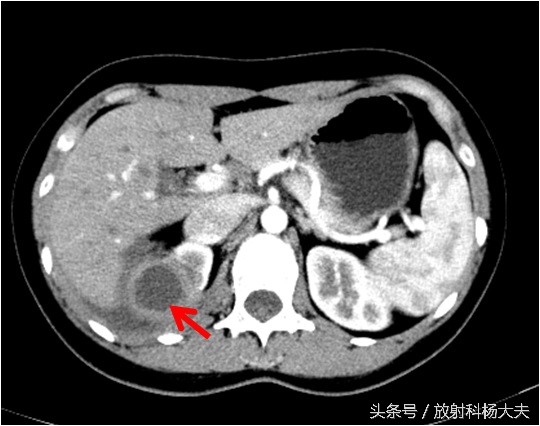

如下图,右肾上长了个东西,囊性的,壁挺厚。

女孩的肾功能是好的,能够看到VR图像里双肾盂和输尿管显影很清楚。